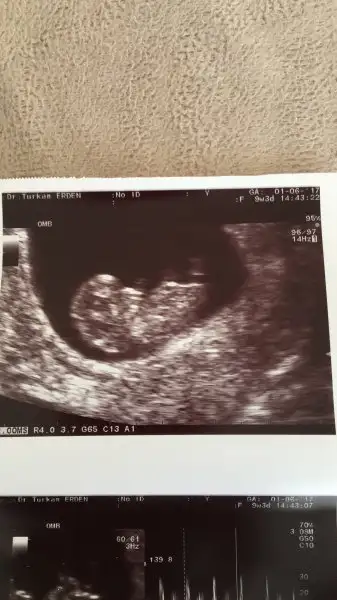

Canım çok üzüldüm Allah sabır versin inşallah en kısa zamanda sağlıklı gebeliğin olur unutturur sana bu durumuKızlar maalesef bebeğimi bir hafta önce kaybetmişim. Kalp atımı da yok. Bugün iki doktor gezdim ikisi de aynı şeyi söyledi ve yarin kurtaj alacağım kanamam da var